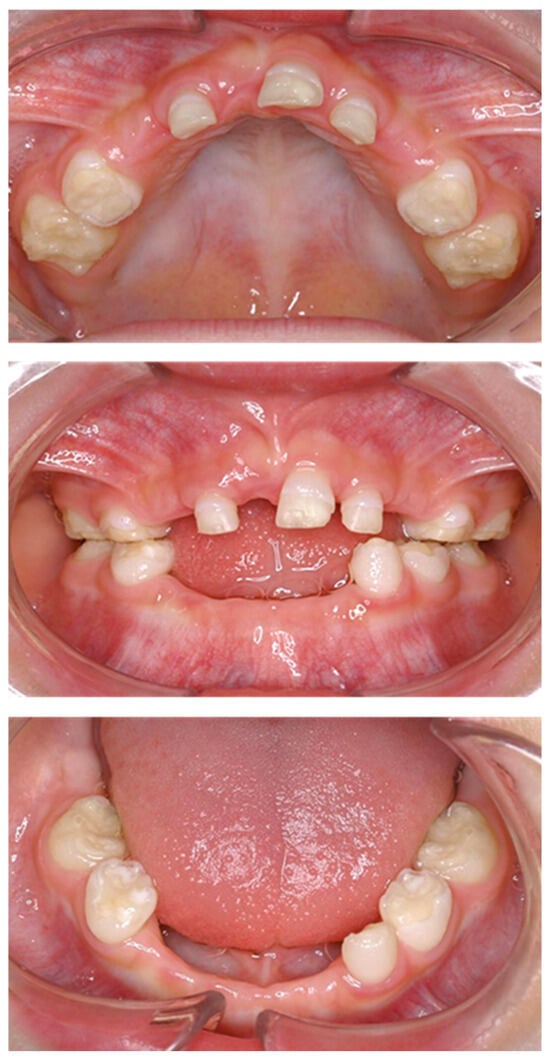

| Tooth | Time |

|---|---|

| Mandibular left primary central incisor | 1 year and 3 months |

| Mandibular right primary central incisor | 1 year and 7 months |

| Mandibular left primary lateral incisor | 2 years |

| Mandibular right primary lateral incisor | 2 years and 4 months |

| Maxillary right primary canine | 2 years and 7 months |

| Mandibular right primary canine | 2 years and 8 months |

| Maxillary right primary central incisor | 3 years |

| Maxillary left primary canine | 3 years |

| Maxillary left primary central incisor | 3 years and 9 months |

| Mandibular left primary canine | 4 years and 3 months |

| Maxillary left primary lateral incisor | 4 years and 6 months |